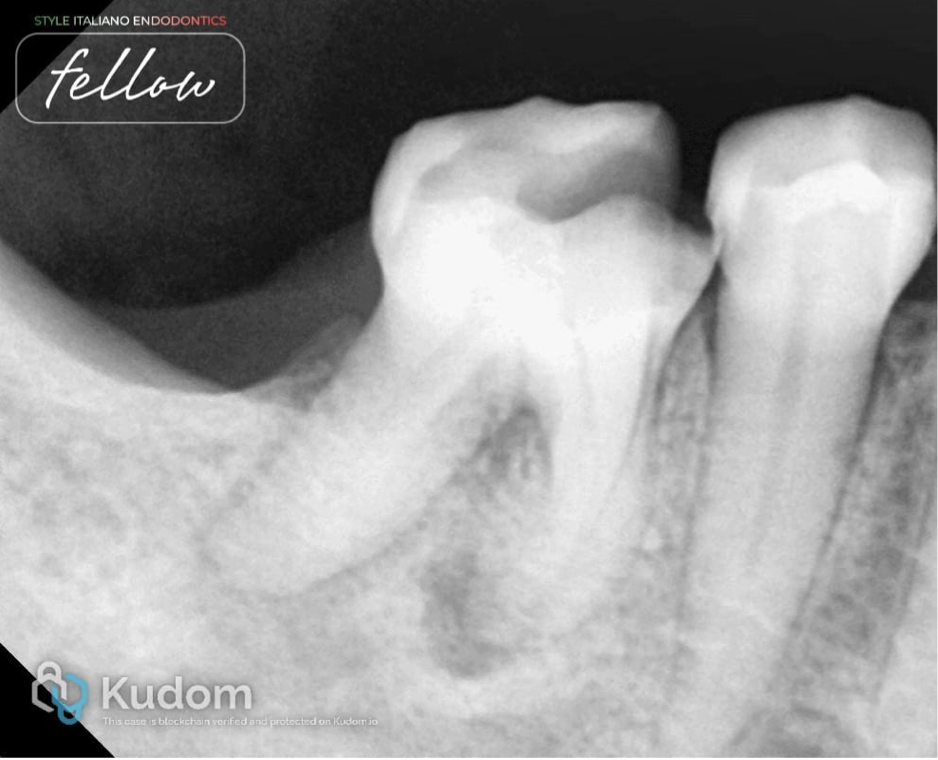

Fig. 6

X-ray taken after completion of the endodontic treatment. It shows healing in both roots. The periapical lesion decreased in size in the mesial and distal root. New bone formation has taken place in the previously lesioned periapical area.